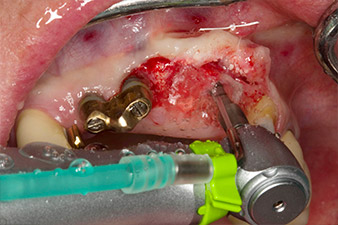

След първичното оздравяване, меките тъкани са оформени посредством базално разположения мост. Два месеца по-късно, обработваното поле е изложено на палатинална алвеоларна инцизия (Фиг 2). Размерите на алвеоларната кост са достатъчни в позиция 22. Фигури 2 и 4 показват препарацията на имплантното ложе, нарязващия винт и имплатирането, използвайки Implantmed.

Новият имплантологичен мотор е използван с подходящите обратни наконечници на W&H.